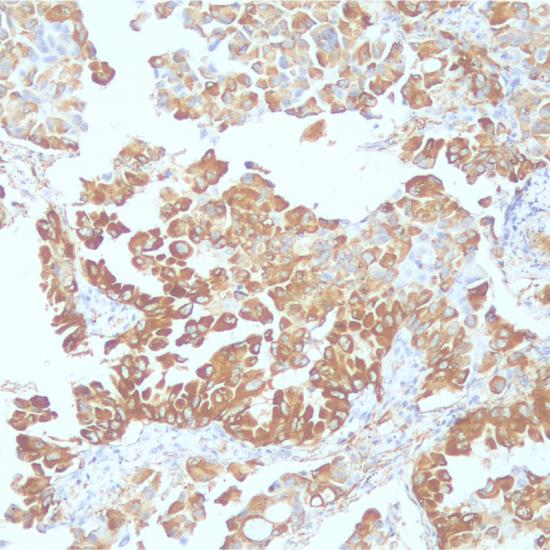

SP-A

肺表面活性蛋白A(SurfactantProteinA)抗體試劑(免疫組織化學(xué)法) 閩廈械備20190174號

細胞漿

肺腺癌

Surfactant Protein A (SP-A)是由肺II型細胞合成并分泌到肺泡中的一種脂蛋白復(fù)合物,主要用于多種類型肺腺癌的研究。